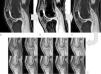

Material and methodsWe included 15 subjects classified into three groups according to clinical criteria (pain, functional limitation, and duration of symptoms) and imaging criteria as follows: (a) normal (3 men, 2 women; age 30±14 years), (b) with initial degeneration of the patellar cartilage (3 men, 2 women; age 30±6 years), or (c) with advanced degeneration (3 men, 2 women; age 57±10 years). All underwent MRI examination using special echo-gradient sequences to segment the cartilage and calculate the T1 maps. We selected the entire cartilage and the regions of interest classified according to clinical and imaging criteria as normal, initial degeneration, and advanced degeneration. The T1 values of the cartilage were obtained pixel by pixel and were calculated as the mean for the entire cartilage or by subregions (normal, initial, advanced). Differences between groups for the entire cartilage and the regions were analyzed using Student-Newman-Keuls post-hoc ANOVA. Reproducibility was evaluated using the coefficient of variance.

ResultsNo significant differences in the overall analysis of the entire cartilage were found between the three groups (normal: 1003±172ms, initial: 1064±124ms, advanced: 1041±308ms, p=0.665). However, the analysis by regions revealed significant differences (normal: 908±53ms, initial degeneration: 1057±157ms, advanced degeneration: 1133±116ms, p=0.029). The reproducibility analysis found variations of 1.3% for the overall calculation, 3.7% for the regional calculation, and 8.2% for the acquisition.

ConclusionIn this preliminary study, calculating the T1 of the cartilage enabled regions with different degrees of degeneration to be differentiated.